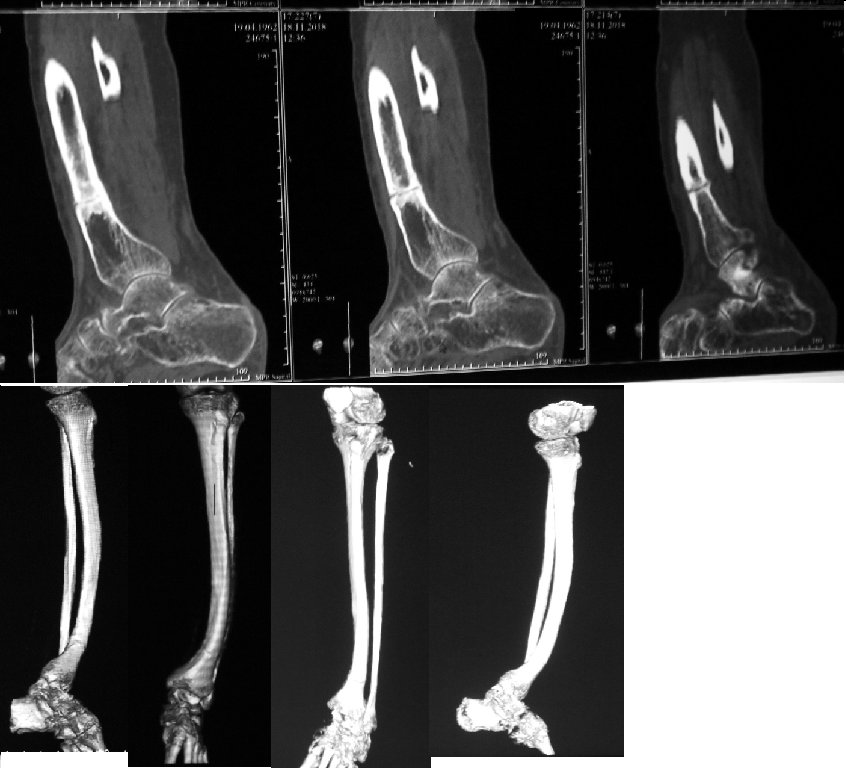

Пациентка 1962 г.р. данная патология костей голени с детства,

планировалось оперативное лечение в 18 лет (Вредена), операцию отменили,

рекомендовали консервативное лечение. рентгенограммы 2018-2019гг.